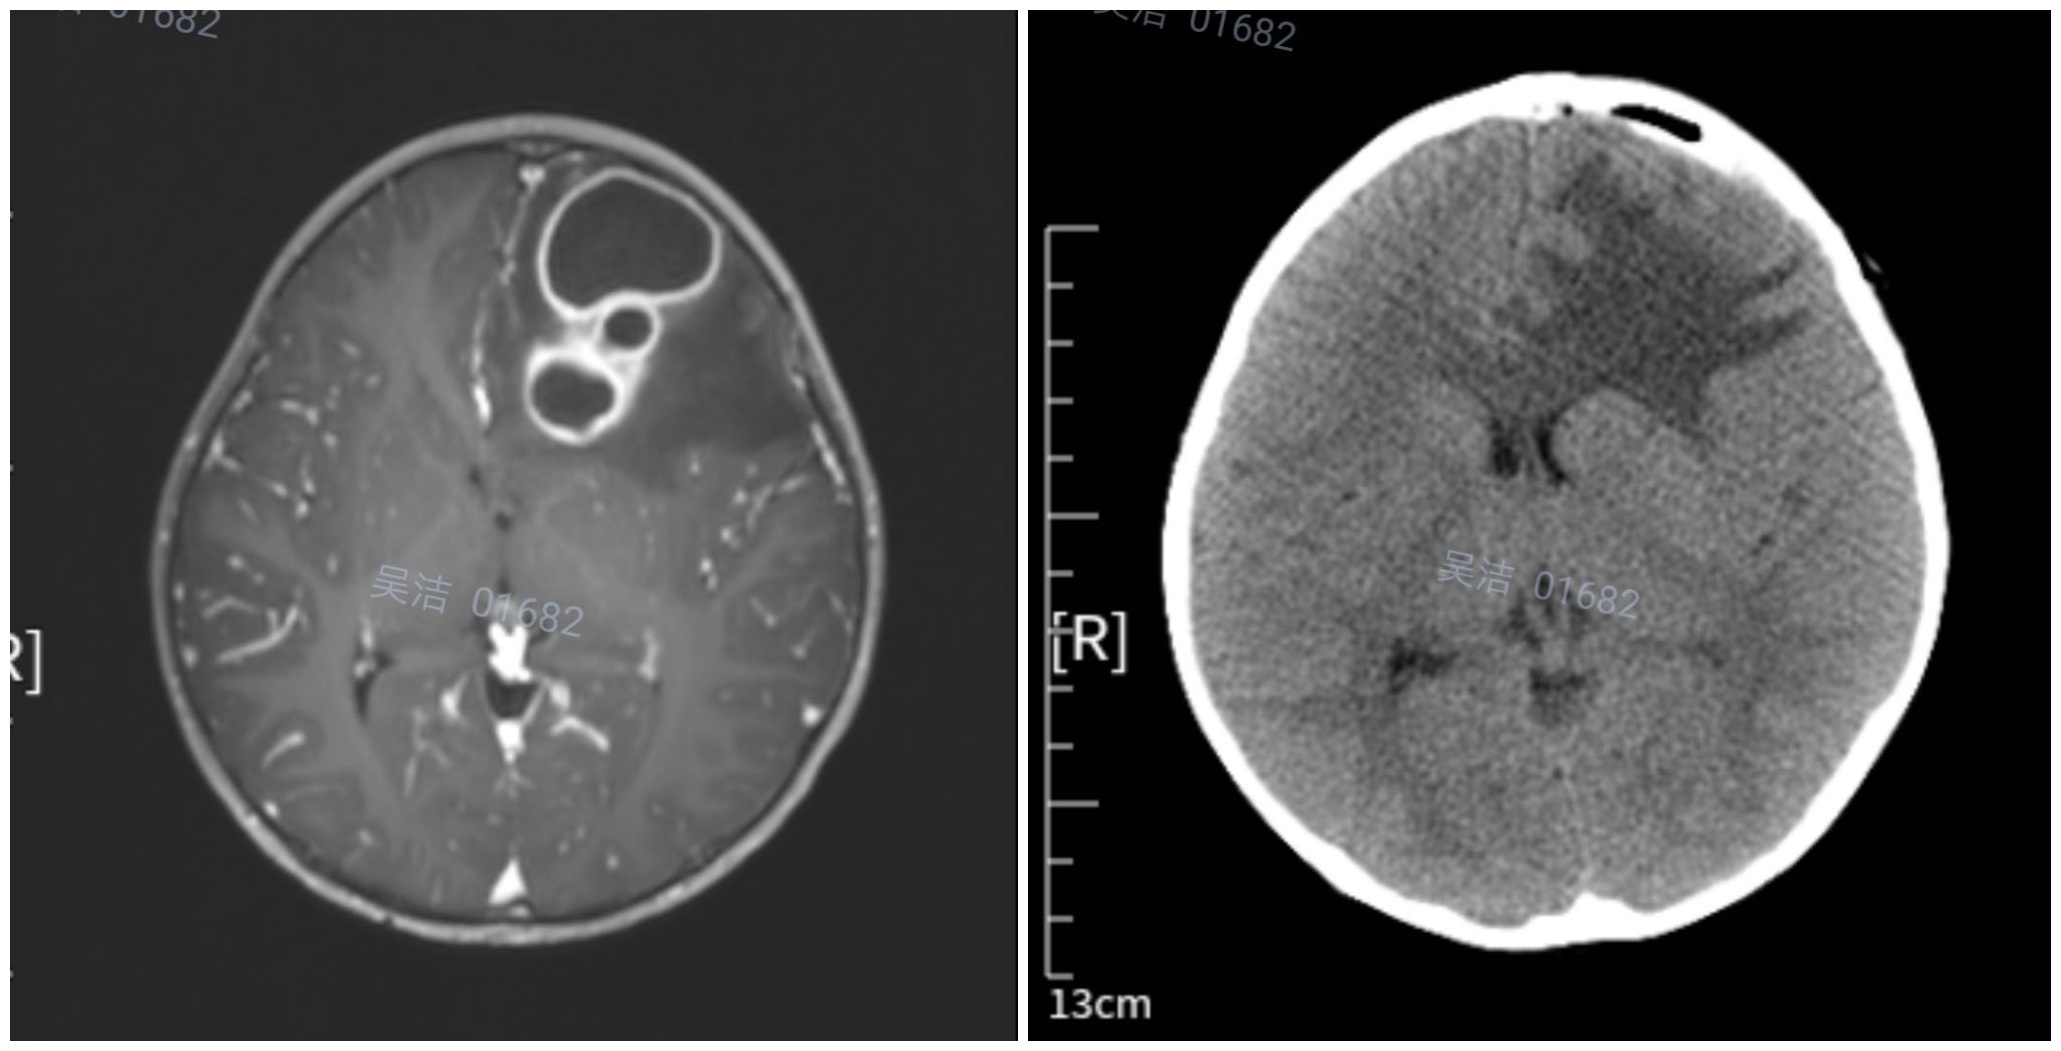

原来,他的女儿欣欣已间断发热、呕吐6天了,并且头痛2天,于3月21日来我院就诊,收住小儿神经科。入院时,患儿高热,频繁呕吐,左侧上眼睑浮肿。核磁提示:颅内占位病变。经询问得知,患儿在12天前有左侧眼部外伤史。入院后主管医师张永琴立即给予患儿降颅压、抗炎等对症治疗,积极完善核磁、腰椎穿刺术等相关检查。腰穿结果显示:脑脊液常规:白细胞数目45*10—6/L。速检脑脊液生化:脑脊液蛋白0.9g/L,诊断:左侧额叶脑脓肿。经请示儿童医院徐丁副院长、陈永前主任,立即指示给予美罗培南联合万古霉素抗感染治疗,遂请神经外科会诊,建议积极抗感染保守治疗2周后行手术治疗。经过对症支持治疗,小欣欣再无发热、呕吐等不适,精神越来越好,眼睑浮肿也慢慢消退,大家都由衷的替欣欣感到高兴。

可是,3月31日早晨,欣欣突然再次呕吐,颅内压增高,小儿神经外科贺振华副主任医师果断建议当日急诊,在全麻下行“经额脑脓肿切除术”。 脑脓肿手术术中必须精细操作,力求彻底切除脓肿,一旦脓肿壁破损和脓液的外渗,颅内感染将无法控制。经过严谨的手术计划和安排,一切准备就绪,欣欣的手术顺利进行。贺振华主任常规分层开颅,围绕肿物剪开硬脑膜,可见皮质下0.5CM多房囊性肿块,给予脑针穿刺脓肿腔,抽出20ML黄绿色脓液,并沿脓肿壁边缘游离,最终完整切除巨大脓肿。经止血、修补、关颅并包扎后,待患儿麻醉清醒,将患儿安全送返病房。

手术前后

术后,儿童医院为患儿制定了的周密的治疗方案,经过抗炎、止血等一系列对症治疗后,欣欣病情慢慢好转,已经能下床走路了,看着女儿的小脸慢慢露出了天真可爱的笑容,欣欣爸爸心里别提有多高兴了!他感慨生命,感恩所有帮助他的医生护士,为表示感谢,他特意送来锦旗。